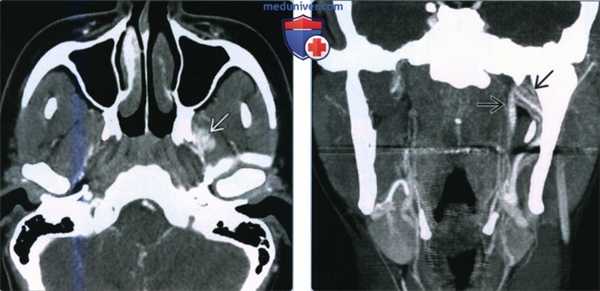

(Слева) При КТ с КУ в аксиальной проекции в медиальных отделах жевательного пространства наблюдается участок накопления контраста, напоминающий объемное образование. На самом деле он представляет собой асимметричное увеличенное крыловидное венозное сплетение.

(Справа) КТ с КУ в коронарной проекции, реконструкция из предыдущего аксиального среза. В этой проекции лучше визуализируются сливающиеся друг с другом сосуды, имеющие здесь линейную форму. Асимметричное увеличение левого венозного крыловидного сплетения, которое является случайной находкой.